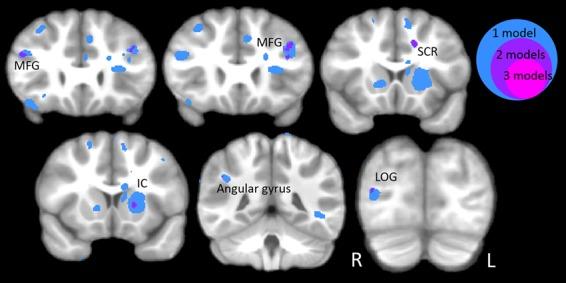

Irritability is garnering increasing attention in psychiatric research as a transdiagnostic marker of both internalizing and externalizing disorders. These disorders often emerge during adolescence, highlighting the need to examine changes in the brain and in psychological functioning during this developmental period. Adolescents were recruited for a longitudinal study examining the effects of early life stress on the development of psychopathology. The 151 adolescents (73 M/78 F, average age = 11.5 years, standard deviation = 1.1) were scanned with a T1-weighted MRI sequence and parents completed reports of adolescent irritability using the Affective Reactivity Index. Of these 151 adolescents, 94 (46 M/48 F) returned for a second session (average interval = 1.9 years, SD = 0.4). We used tensor-based morphometry to examine cross-sectional and longitudinal associations between irritability and regional brain volume. Irritability was associated with brain volume across a number of regions. More irritable individuals had larger hippocampi, insula, medial orbitofrontal cortex and cingulum/cingulate cortex and smaller putamen and internal capsule. Across the brain, more irritable individuals also had larger volume and less volume contraction in a number of areas that typically decrease in volume over the developmental period studied here, suggesting delayed maturation. These structural changes may increase adolescents' vulnerability for internalizing and externalizing disorders.